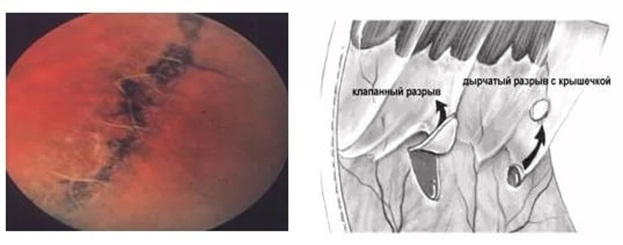

Under the action of physical exertion, falls, conditions associated with lifting to a height or underwater immersion, acceleration, jerks and weight transfer, vibration, dystrophic altered areas can cause ruptures.

在体力消耗,跌倒,抬高或在水下浸入,加速,猛拉和重量转移,振动,营养不良的改变区域相关的条件下,可能导致破裂。

If in the dystrophy zone there are adhesions with the vitreous body, then often tractions (cords, adhesions) form between the modified vitreous body and the retina. It is highly likely that for any deformity it will pull the retina behind itself into the eye. Such adhesions, joining one end to the thinned area of the retina, many times increase the risk of ruptures and subsequent detachment. And this is all the chances of losing sight or degrading the optical quality of the eye to a few percent of the norm.

如果在营养不良区与玻璃体发生粘连,那么在修饰的玻璃体和视网膜之间通常会形成牵引力(绳索,粘连)。 对于任何畸形,极有可能将其自身后面的视网膜拉入眼睛。 这种粘连将一端连接到视网膜变薄的区域,多次增加了破裂和随后脱落的风险。 这是所有失去视力或将眼睛的光学质量降低到正常水平的百分之几的机会。

In myopic people, as a rule, the axial length of the eye is more than 24 mm (the average parameter, the measurement of which tells us about the progression of myopia). There is a risk that the eye, increasing (and an increase in the eye — this is, in fact, myopia) begins to pull the vitreous body (because the rest of the tissues stretch very little). Dystrophic chorioretinal processes on the periphery of the retina (“lattice degeneration”, “snail track”, etc.) lead to thinning of the retina and its ruptures.

通常,在近视人群中,眼睛的眼轴长度超过24毫米(平均参数,其测量值可以告诉我们近视的发展)。 存在眼睛增大(和眼睛增大,实际上是近视)的风险开始拉动玻璃体的原因(因为其余组织的拉伸很小)。 视网膜外围的营养不良性脉络膜视网膜病变(“晶格变性”,“蜗牛痕迹”等)导致视网膜变薄及其破裂。

With them, one can live as a whole without any symptoms, but the risk of retinal detachment in these cases is very high.

有了它们,人们可以整体生活而没有任何症状,但是在这些情况下视网膜脱离的风险非常高。